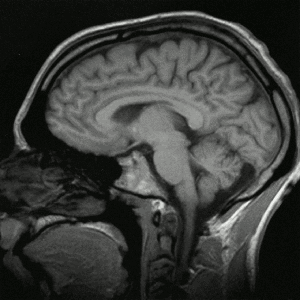

Imagen por resonancia magnética

Una imagen por resonancia magnética (IRM), también conocida como tomografía por resonancia magnética (TRM) o imagen por resonancia magnética nuclear (IRMN), es una técnica no invasiva que utiliza el fenómeno de la resonancia magnética nuclear para obtener información sobre la estructura y composición del cuerpo a analizar. Esta información es procesada por ordenadores y transformada en imágenes del interior de lo que se ha analizado.

En vez de aplicar tres gradientes diferentes que establezcan una relación única entre frecuencia de resonancia y punto del espacio, es posible utilizar diferentes frecuencias para las bobinas de gradiente, de manera que la información queda codificada en espacio de fases (se pueden ver imágenes en cortes sagitales, coronales y axiales). Esta información puede ser transformada en posiciones espaciales utilizando la transformada de Fourier discreta.

Imágenes neurológicas

IRM es la herramienta escogida para cánceres neurológicos frente a tomografía computarizada, al ofrecer mejor visualización de las áreas situadas en la parte posterior de la fosa craneal, conteniendo el tronco encefálico y el cerebelo. El contraste propiciado por la sustancia gris y la sustancia blanca hace las imágenes de IRM sean la mejor opción para muchas condiciones del sistema nervioso central, incluyendo enfermedades desmielinizantes, demencia, enfermedades cerebrovasculares, enfermedades infecciosas, enfermedad de Alzheimer y epilepsia.[23][24] Al ser una técnica que realiza imágenes separadas tan solo por unos pocos milisegundos puede apreciarse cómo reacciona ciertas zonas del cerebro a diferentes estímulos, permitiendo a los investigadores el estudio estructural como funcional de las anormalidades de los trastornos psicológicos.[25] También es utilizado para cirugías estereotácticas guiadas y radiocirugía para el tratamiento de tumores intracraneales, malformaciones arteriovenosas, y otras casos de condiciones que pueden ser tratadas quirúrgicamente usando una herramienta conocida como N-localizer.[26][27][28]